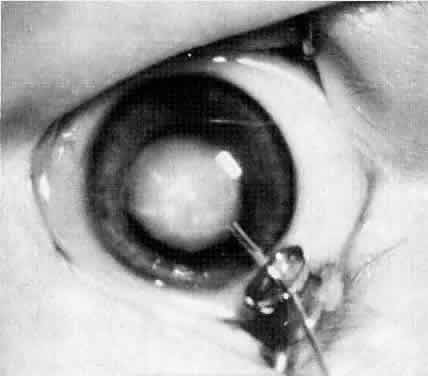

Usually, anterior polar cataracts are visually insignificant and allow normal visual development (see Fig. 1). However, some affect vision, and all require careful monitoring.7 Centrally located cataracts that are on or near the posterior lens capsule have a greater effect on the refraction of light and visual acuity (Fig. 2). Nuclear cataracts associated with metabolic disorders or prenatal infections produce double refracting systems that cause optical distortion and significantly decrease visual acuity (Fig. 3).

Ultimately, it is the measured or estimated level of visual acuity or acuity potential that determines the need for cataract surgery. If either the measured or the estimated decrease in visual acuity produced by the cataract is sufficient to prevent adequate visual development or if signs of significantly decreased visual acuity, such as strabismus or poor central fixation, are present, cataract surgery is indicated. Use of the Teller visual acuity cards at periodic intervals can help to measure visual acuity.10 In some children, visual acuity that is below normal or decreasing can be documented accurately to support the decision to perform cataract surgery (Figs. 4 and 5). Care must be taken in interpreting Teller visual acuity data because the normal levels in young infants and children are low and span a wide range. The Teller acuity card measurement of grating visual acuity may severely underestimate the level of visual loss in patients with cataracts and amblyopia.11